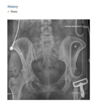

A 75-year-old man with history of bilateral total hip replacement and worsening hip pain

AP radiograph of the pelvis (Fig. 2.30.1) demonstrates an unusually vertical orientation of the acetabular component on the left. Additionally, the bones of the left hemipelvis are enlarged and have coarsened trabeculae. An axial CT through the left hip (Fig. 2.30.2) confirms rotation of the acetab- ular component and the coarsened bone trabeculae. Loose total hip replacement, Paget disease the left acetabular opening is more vertically oriented than the normal 30- to 50-degree angle rel- ative to a horizontal line drawn through the ischial tuberosities. signs of loosening, which include widening of the lucent zone at the cement-bone or prosthesis-bone interface >2 mm (present surrounding the inferome- dial aspect of the acetabular component in this case), migration of the components (present in this case), cement fracture, periosteal new bone formation, and gross osteolysis involving the surrounding bone.